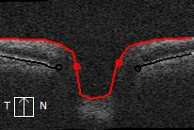

Die Untersuchung mit der optischen Kohärenztomografie (OCT) erlaubt eine schnelle, präzise und objektive Beurteilung sowohl des Sehnervs, als auch der Nervenfaserschicht.

- Die Untersuchung mit der OCT erlaubt eine objektive Messung des Sehnervs und der Dicke der Nervenfaserschicht. Veränderungen infolge eines Glaukoms werden so rechtzeitig erkannt und behandelt. Die Untersuchung dauert nur wenige Minuten und belastet den Patienten nicht.

Mittels der OCT werden die einzelnen Schichten im Bereich des Sehnerven und der Nervenfaser einschließlich möglicher Veränderungen im Verlaufe einer Glaukom-Erkrankung dargestellt.